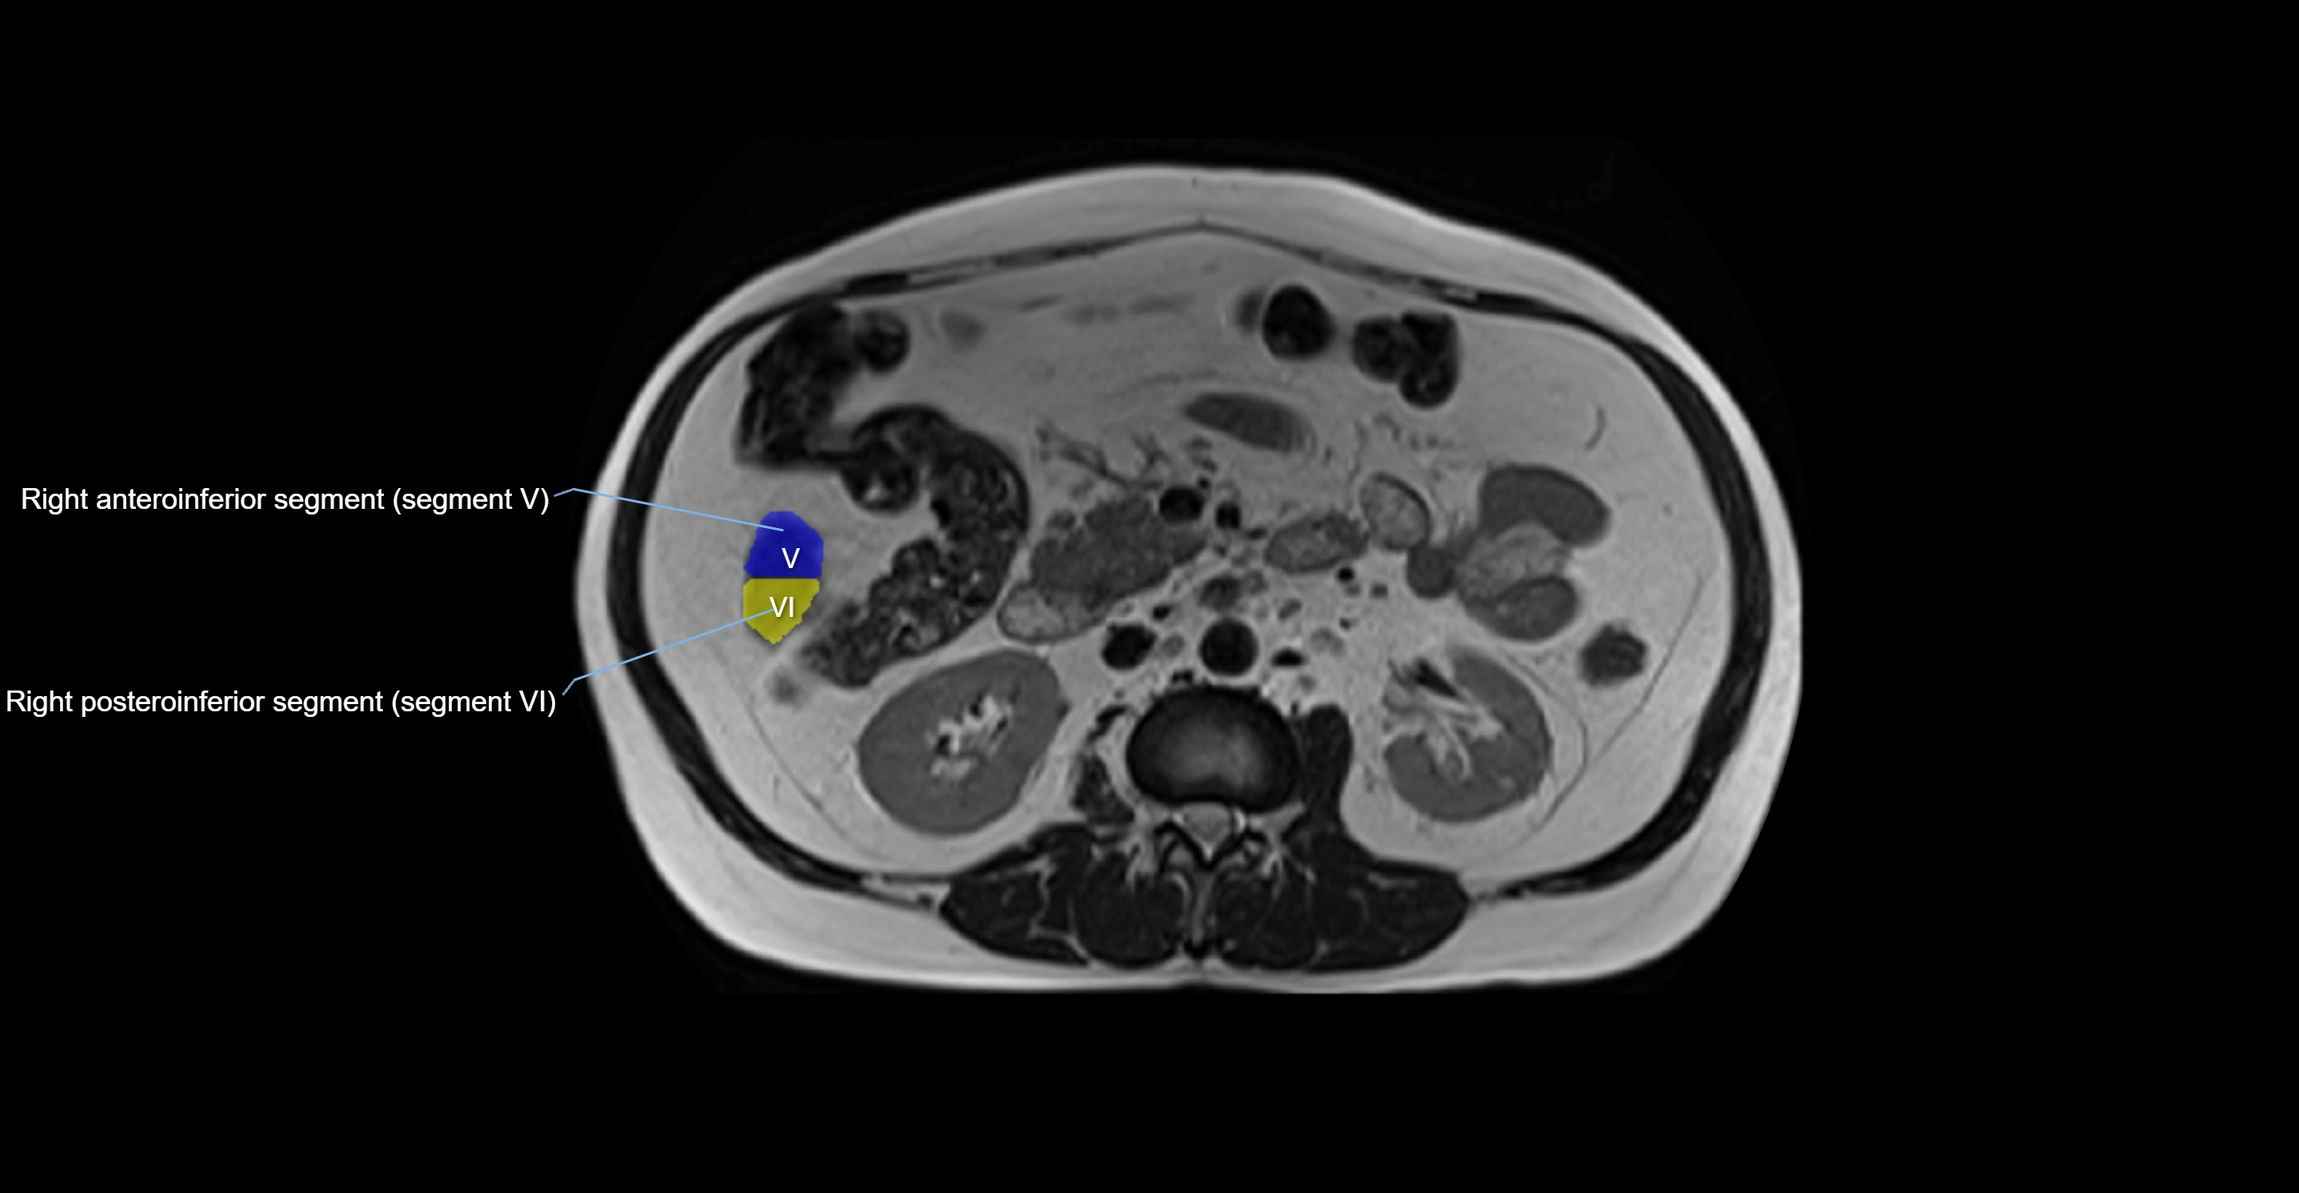

CT Appearance

CT Pre-Contrast:

• Caudate lobe appears as a soft-tissue density, isodense to the rest of the liver

• Enlargement may be appreciated in cirrhosis or Budd–Chiari syndrome

CT Post-Contrast:

• Homogeneous enhancement in the portal venous phase, similar to rest of liver

• Independent venous drainage into the IVC may be visualized

• Lesions follow characteristic CT enhancement patterns (HCC: arterial hyperenhancement with washout; hemangiomas: peripheral nodular enhancement with centripetal fill-in)

CT Venous Phase (functional significance):

• Caudate lobe often enhances relatively more than other lobes in Budd–Chiari syndrome, due to preserved venous outflow